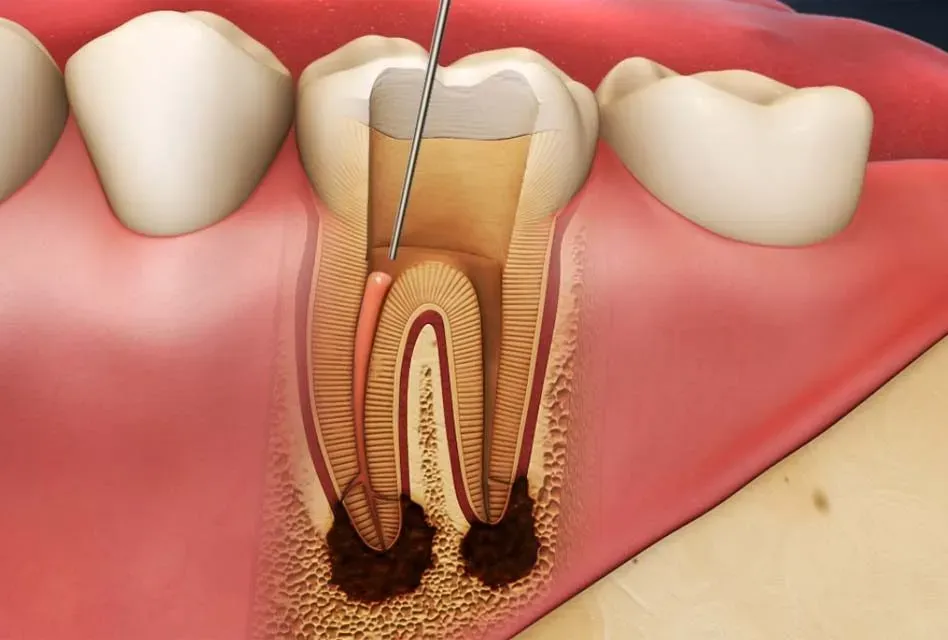

Nhiễm trùng chân răng là một bệnh lý răng miệng do việc điều trị sâu răng và tủy răng chưa kỹ hoặc chưa điều trị kịp thời. Các loại vi khuẩn, virus không được loại bỏ sẽ tấn công chân răng sau đó lan qua các vùng khác gây ra tình trạng nhiễm trùng.

Trong nhiều trường hợp, bị nhiễm trùng nặng, các bác sĩ phải tiến hành chụp X- Quang để xác định vị trí nhiễm trùng

Các bác sĩ sẽ tiến hành chích mủ và làm sạch phần bị nhiễm trùng. Trong nhiều trường hợp các bác sĩ sẽ thực hiện chữa tủy răng, trám răng, bọc sứ nếu cần thiết.